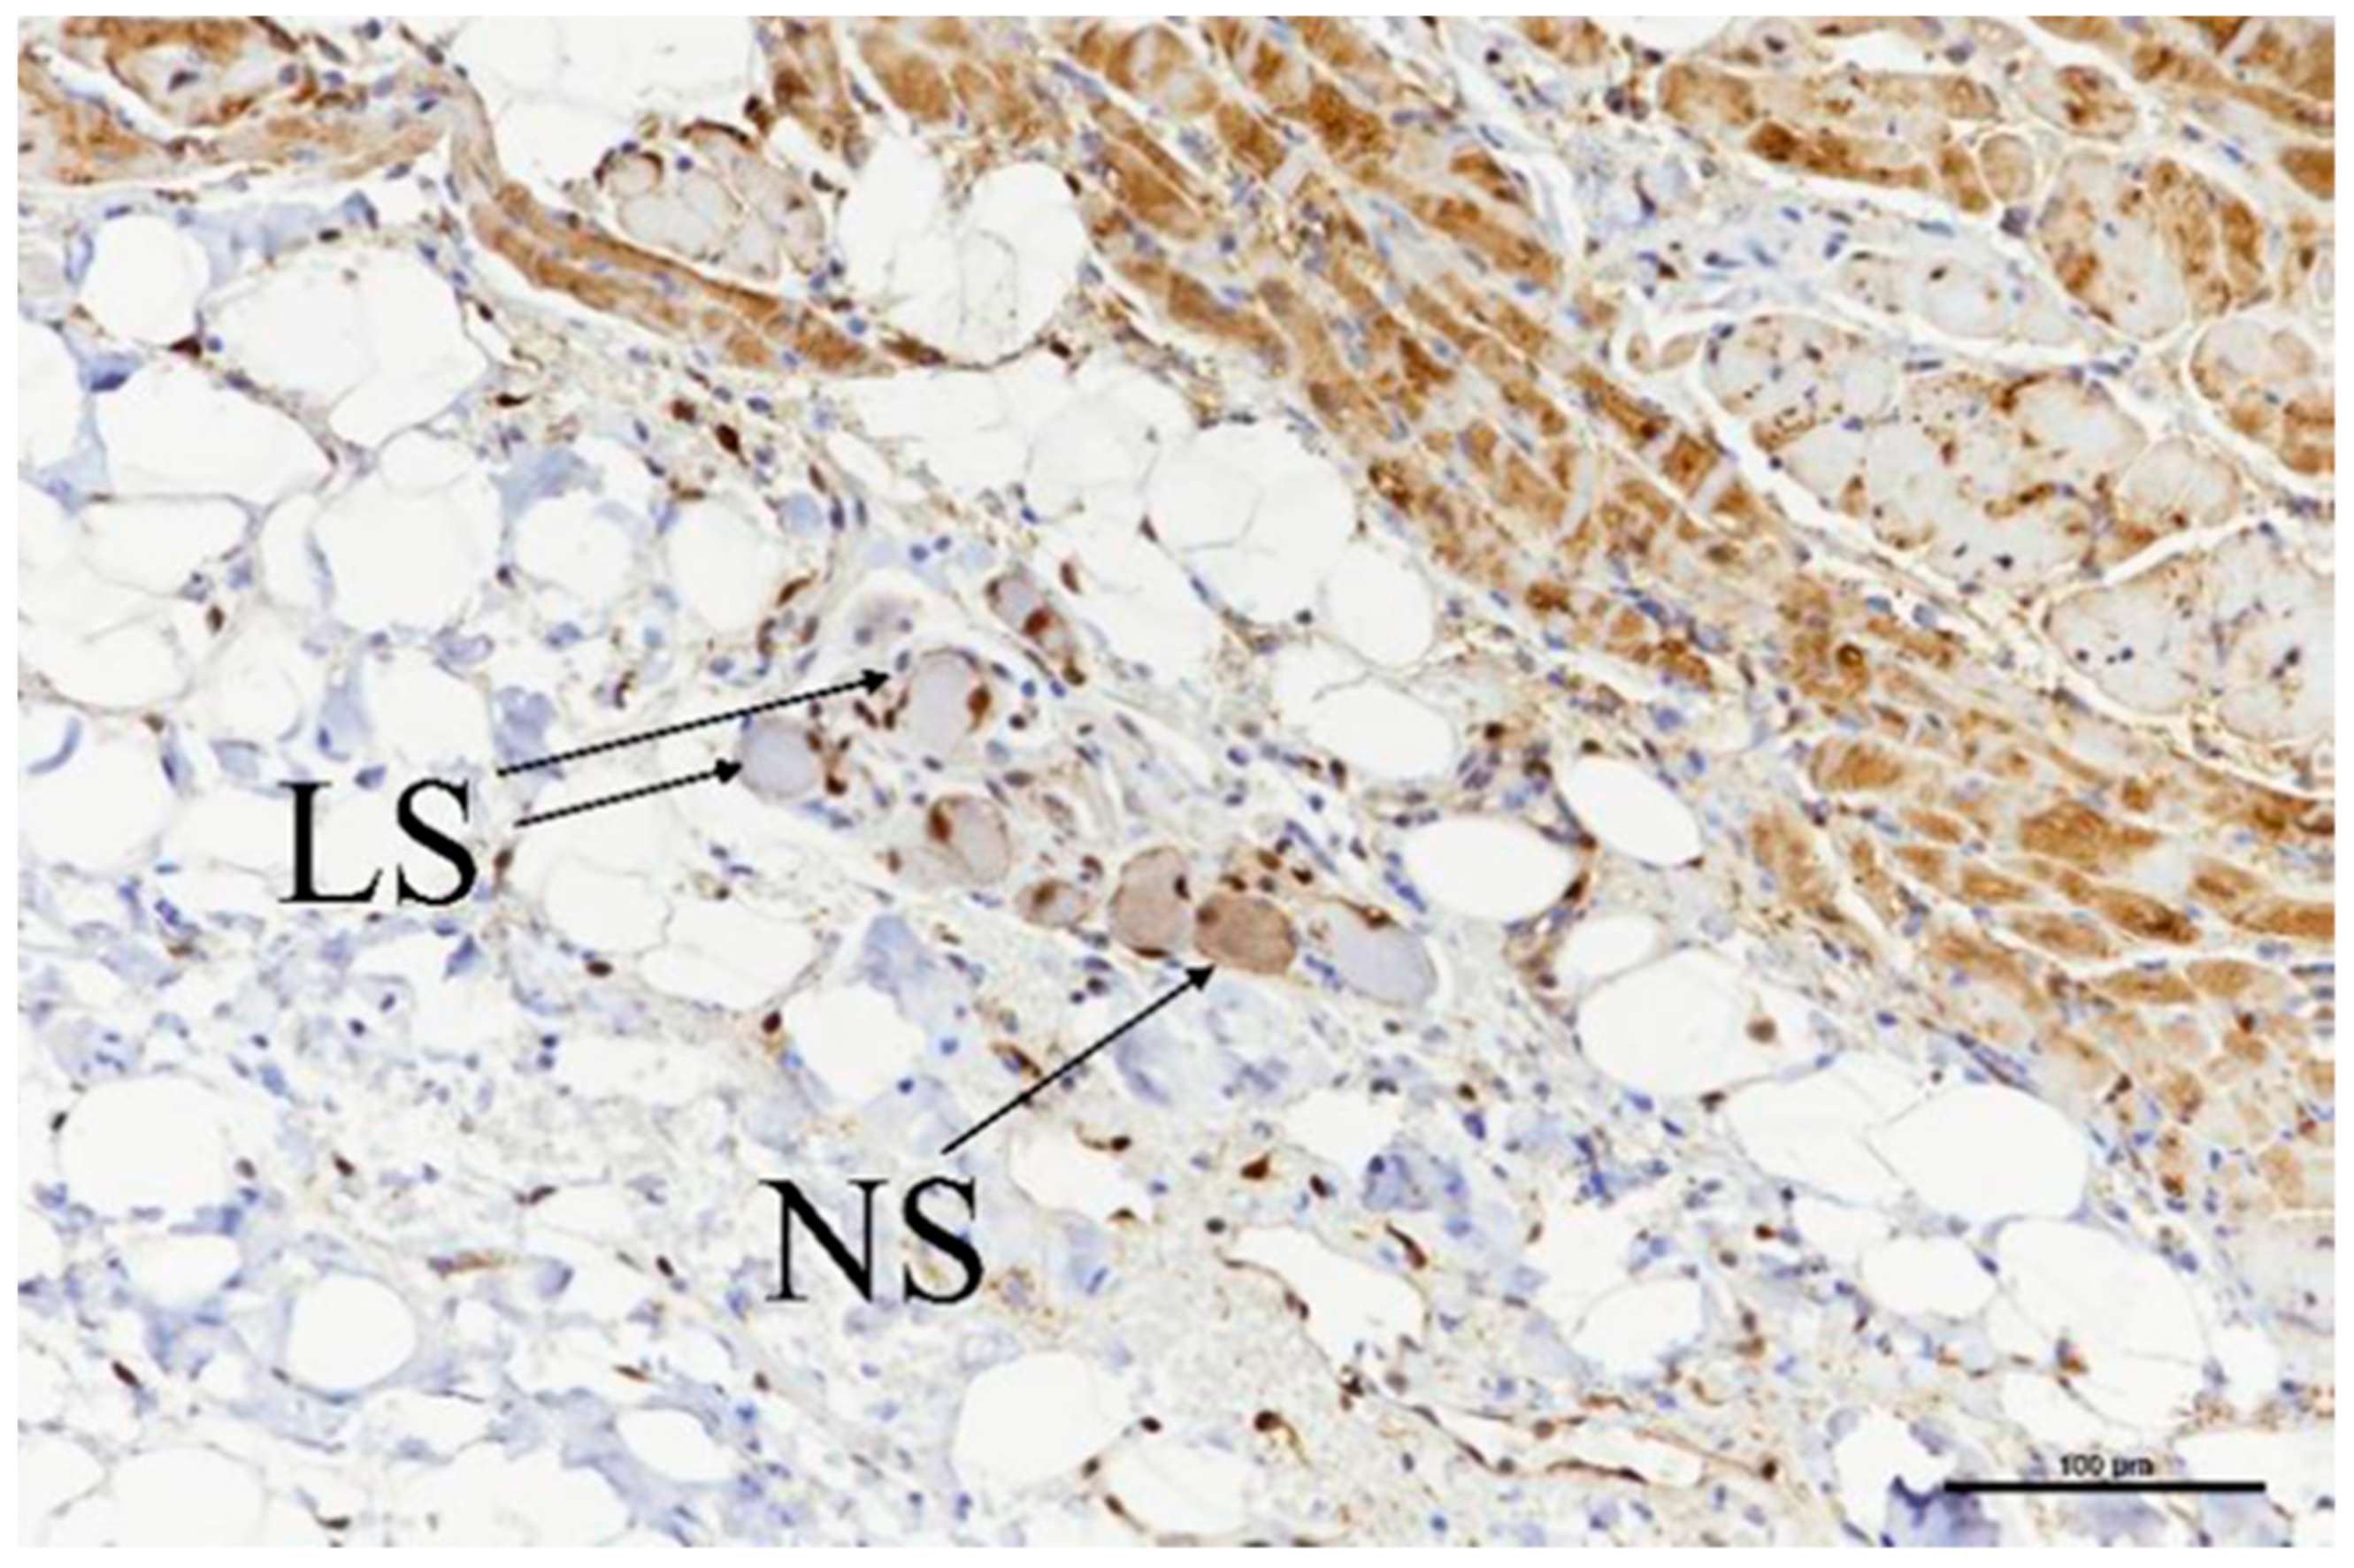

2.4. Histological Evaluation

3.3. Histologic Evaluation

3.4. Porcine Study—Catheter Access and Navigation